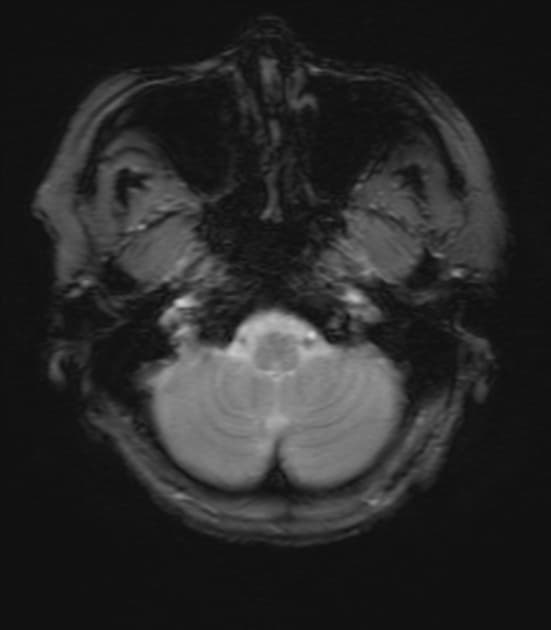

Axial non-contrast

Áp xe não (brain abscess)

- Tổn thương nội trục dạng tròn với phù vận mạch (vasogenic edema).

- Chụp cộng hưởng từ có tiêm thuốc đối quang cho thấy ngấm thuốc viền (rim enhancement) mỏng, đều, trơn.

- Các mặt cắt bổ sung theo mặt phẳng vành và trục cho thấy không có nốt thành (mural nodule).

- Tổn thương nội trục dạng tròn với phù vận mạch, thành mỏng tăng tín hiệu (hyperintense) ở chuỗi xung T1 và giảm tín hiệu (hypointense) ở T2.

- Chụp cộng hưởng từ sau tiêm gadolinium cho thấy ngấm thuốc viền (rim enhancement).